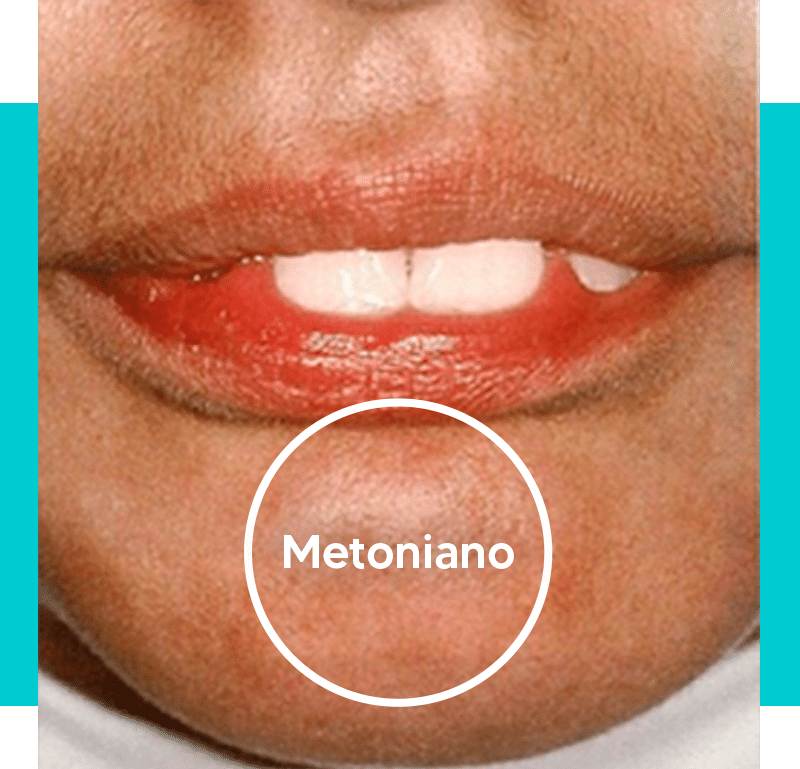

Los malos hábitos miofuncionales pueden comenzar ya en el parto, cuando la madre da a luz por cesárea.

Al pasar por este proceso, el bebé puede ver comprometido el desarrollo de sus músculos orofaciales, ya que al nacer se le estimula a respirar por la boca en lugar de por la nariz, provocando los problemas que mostramos anteriormente.